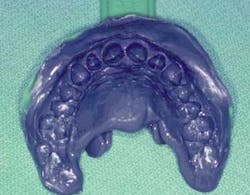

Pre-operatory labwork

Maxillary and mandibular alginate impressions were taken and poured up in stone. The pre-operative models, cosmetic simulation, and a bite registration were sent to the laboratory for the fabrication of diagnostic wax-ups. The diagnostic wax-up shows any changes to be made in the contour and width of the abutment teeth. The incisors were lengthened and reshaped in ivory wax as directed by the digital images. The wax-up was then duplicated to facilitate the manufacture of a preparation guide and a hard/soft matrix. Together, the image-inspired wax-up and the simulated picture allow the dentist and the patient to see how treatment will look when finished. These two tools provide the accurate communication between the dentist and the laboratory necessary to obtain superior esthetic and functional results. Once the patient has approved the cosmetic image and the wax-up, the dentist is on his way to providing transitional and final restorations that will fulfill the patient's esthetic desires.